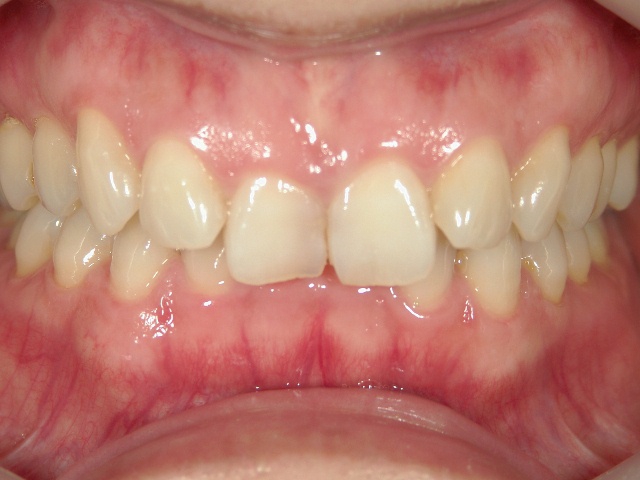

矯正歯科(全顎ワイヤー矯正)治療後

全顎ワイヤー矯正 症例(2)

36歳女性 磐田市

在住

治療期間2年6

ヶ月

矯正歯科 治療後